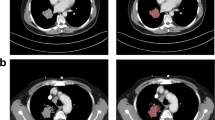

A local cohort of 85 patients were retrospectively (2010–2017) analyzed after approval by the institutional research review board. CT images acquired with the same protocol were semiautomatically segmented by a volumetric segmentation method. Tumors were characterized by quantitative CT features of shape, first-order, second-order, and higher-order textures. Statistical and machine learning analyses assessed the features individually and combined with clinical data.